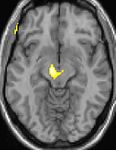

Positron emission tomography (PET) shows brain areas being activated during pain

Voxel-based morphometry (VBM) shows brain area structural differences

Positron emission tomography (PET) scans indicate the brain areas which are activated during attack only, compared to pain free periods. These pictures show brain areas that are active during pain in yellow/orange color (called "pain matrix"). The area in the center (in all three views) is specifically activated during CH only. The bottom row voxel-based morphometry (VBM) shows structural brain differences between individuals with and without CH; only a portion of the hypothalamus is different.[33]